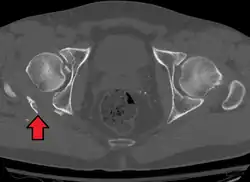

Axial CT image (viewed on bone windows) of a complex comminuted left acetabular fracture involving both anterior and posterior columns.

Axial CT image (viewed on bone windows) of a complex comminuted left acetabular fracture involving both anterior and posterior columns. -